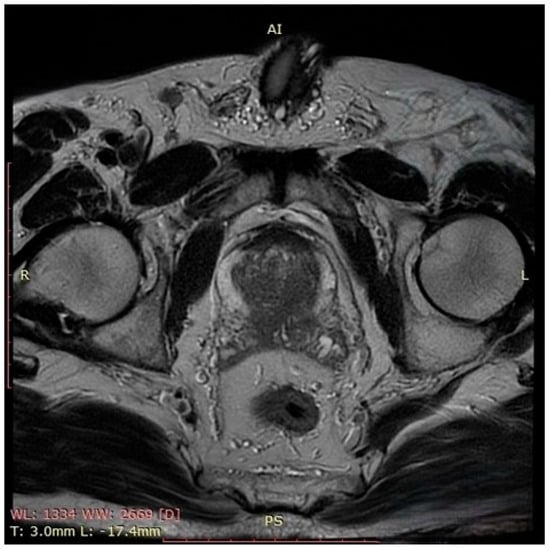

In October 2023, the patient presented with complete urinary retention and an indwelling urethrovesical catheter in place. A thoraco-abdomino-pelvic staging CT scan identified two pulmonary nodules and multiple cervico-thoraco-abdomino-pelvic lymph nodes without any sign of active hematological disease. A PET-CT scan performed at that time showed multiple bilateral latero-cervical lymph nodes, without evidence of significant diffuse 18F-FDG uptake. Unfortunately, despite our efforts, we were unable to retrieve the original imaging files or the formal radiology report. The patient exhibited no systemic symptoms such as night sweats, fatigue, fever, or weight loss and remained active. His medication regimen included ibrutinib for non-Hodgkin lymphoma, Perindopril for grade I hypertension, Omeprazole as a gastroprotective agent, and Allopurinol for high uric acid levels. The patient was a non-smoker and non-drinker without any family history of autoimmune disorders or cancers, including prostate cancer. The patient’s ECOG performance status grade was also 0, but the MIPI score was 3.47 points, still indicating an intermediate-risk category with a median overall survival of approximately 51 months. Given the patient’s clinical–biological status and considering the risks and limitation of prostate cancer screening, the decision was to measure the PSA level. Following two consecutive measurements of the Prostate-Specific Antigen level that showed elevated levels (11.7 ng/mL), multiparametric prostate Magnetic Resonance Imaging (MRI) (Figure 1) was performed. The prostate MRI demonstrated a bilateral ill-defined lesion in the peripheral zone, with Prostate Imaging Reporting and Data System (PIRADS) 5 characteristics, highly suggestive of malignancy. Considering the laboratory and imaging investigations, MRI fusion-guided transrectal prostate biopsy was indicated and performed. The histopathological findings described secondary prostatic lymphoma.

Figure 1. This axial T2-weighted image of the prostate demonstrates a hypointense lesion located in the peripheral zone, bilaterally, which is ill-defined, with disruption of the normal high-signal intensity of the peripheral zone and focal capsular bulging. There is no clear evidence of extracapsular extension or seminal vesicle invasion. These findings are suggestive of a PIRADS 5 lesion and highly suspicious for clinically significant prostate cancer.